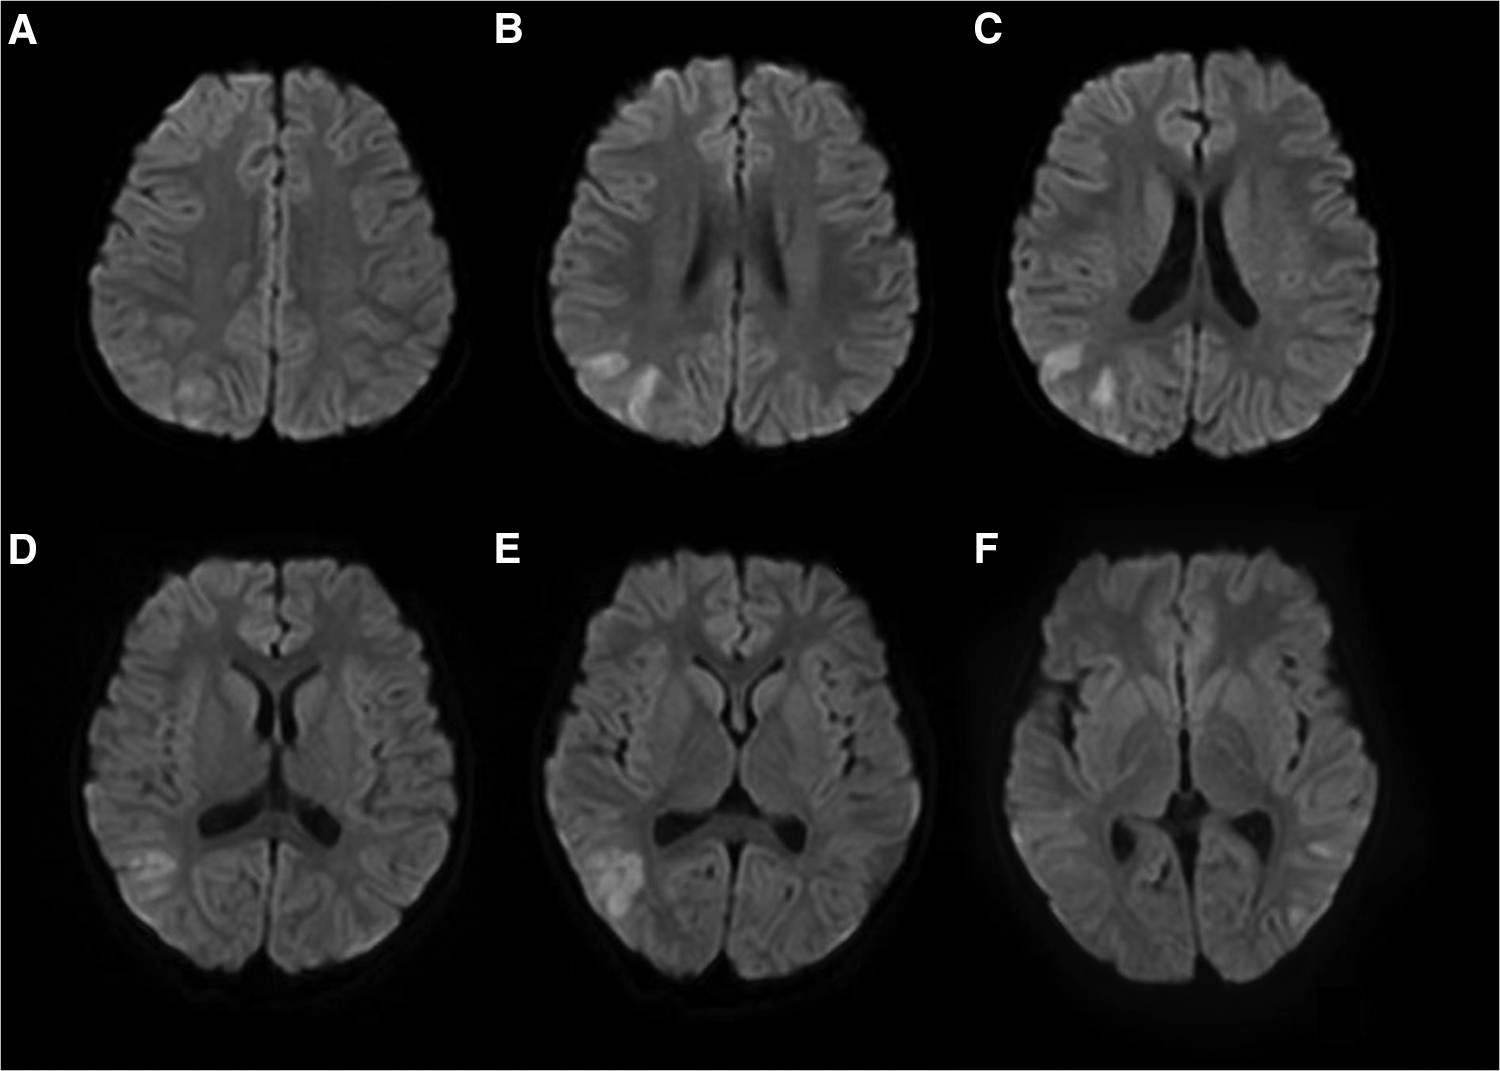

The patient experienced a total of three similar episodes since the age of 1 year and 7 months. The patient's mental and motor development was normal before and after the onset of the disease. Each time, there was a minor head trauma, followed by headache, somnolence, and seizures. Each seizure manifested as a double-eye gaze to the left, intermittent left-sided limb rigidity, and unconsciousness. Each seizure manifested as status epilepticus. Half a day after the resolution of this seizure, the patient developed a fever with a temperature of 39°C. There were no abnormalities in brain magnetic resonance imaging (MRI), magnetic resonance angiography (MRA), and magnetic resonance venography (MRV) during previous episodes. The blood routine, arterial blood gas analysis, blood ammonia, glucose, homocysteine, calcium, and electrolytes showed no significant abnormalities. A brain MRI after this episode showed multiple high signal intensities on diffusion-weighted imaging (DWI) in the right frontotemporal cortex (Figure 1). Neurological examination after this episode showed the patient had left-sided central facial palsy as well as left-sided upper and lower extremity paralysis. Babinski's sign was positive bilaterally, the rest of the pathological symptoms were negative, and the meningeal stimulation sign was negative.

Figure 1

Brain MRI of patient #1 showed multiple high signal intensities on DWI in the right frontotemporal cortex (A–F).

The patient was finally diagnosed with hemiplegic migraine presenting as an acute encephalopathy. He was given daily flunarizine 3 mg (0.2 mg/kg) to prevent HM attacks. After treatment for 1.5 months, a follow-up MRI showed complete disappearance of abnormal signals throughout the right hemispheric cortex (Figure 6). The video EEG was not reviewed because the patient fully recovered to the pre-onset level and the patient's compliance was not high.

Figure 6

The brain MRI of Patient #1 showed complete disappearance of abnormal signals 1.5 months after treatment (A–D).